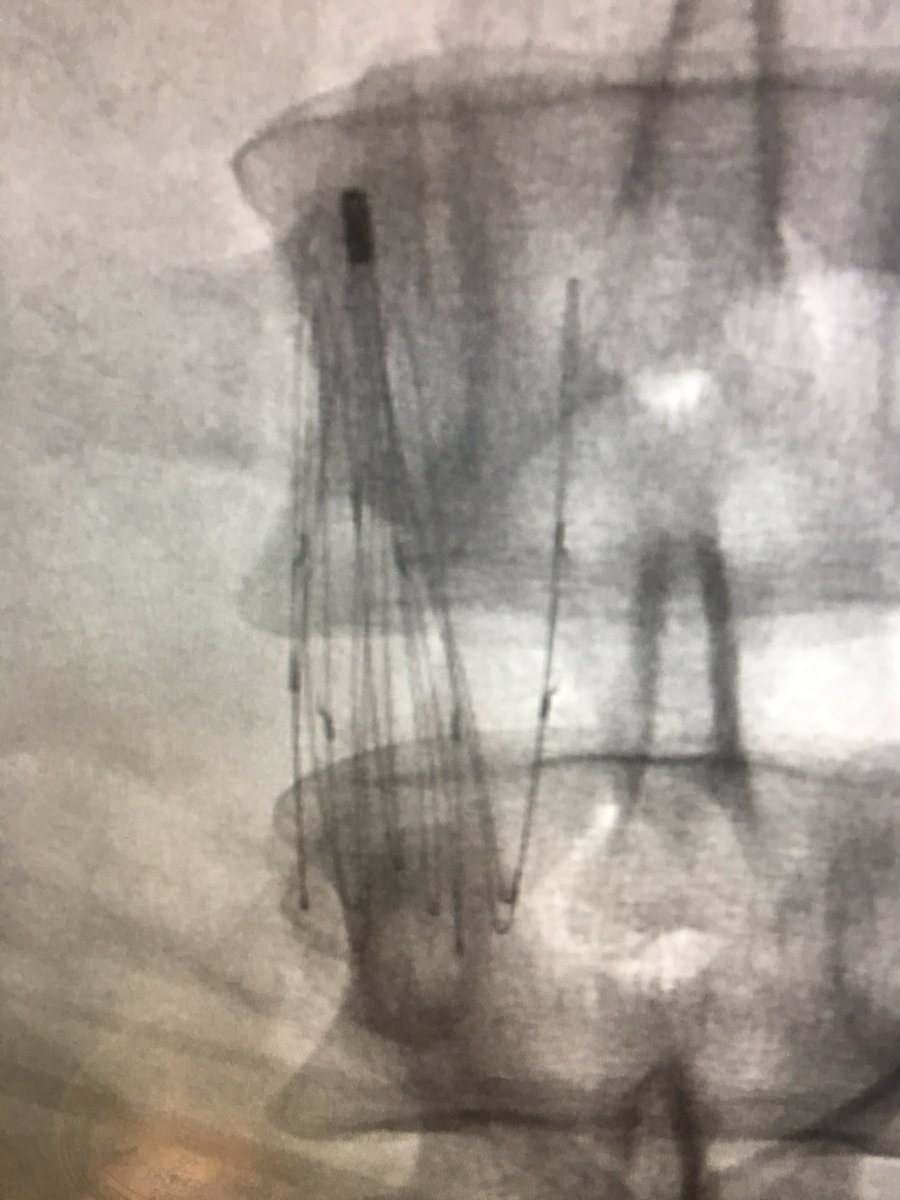

It was hard to say goodbye to this 4 year old filter with strut in the aorta | #iRad #radres #IRmusicvideos #FOAMed #Boyz2men #IRonc